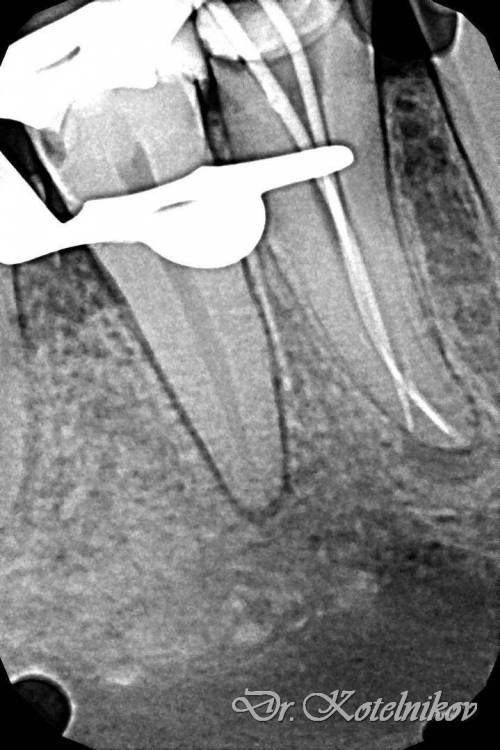

Ico Опубликовано 10 апреля, 2022 Автор Поделиться Опубликовано 10 апреля, 2022 (изменено) 3 отдельных канала в нижнем премоляре,паковка похожая как у Томаса Ланга.Каллибровка,паковка апексов была по S2 протейперу + 25 к. Изменено 10 апреля, 2022 пользователем Ico 1 1 2 Ссылка на комментарий